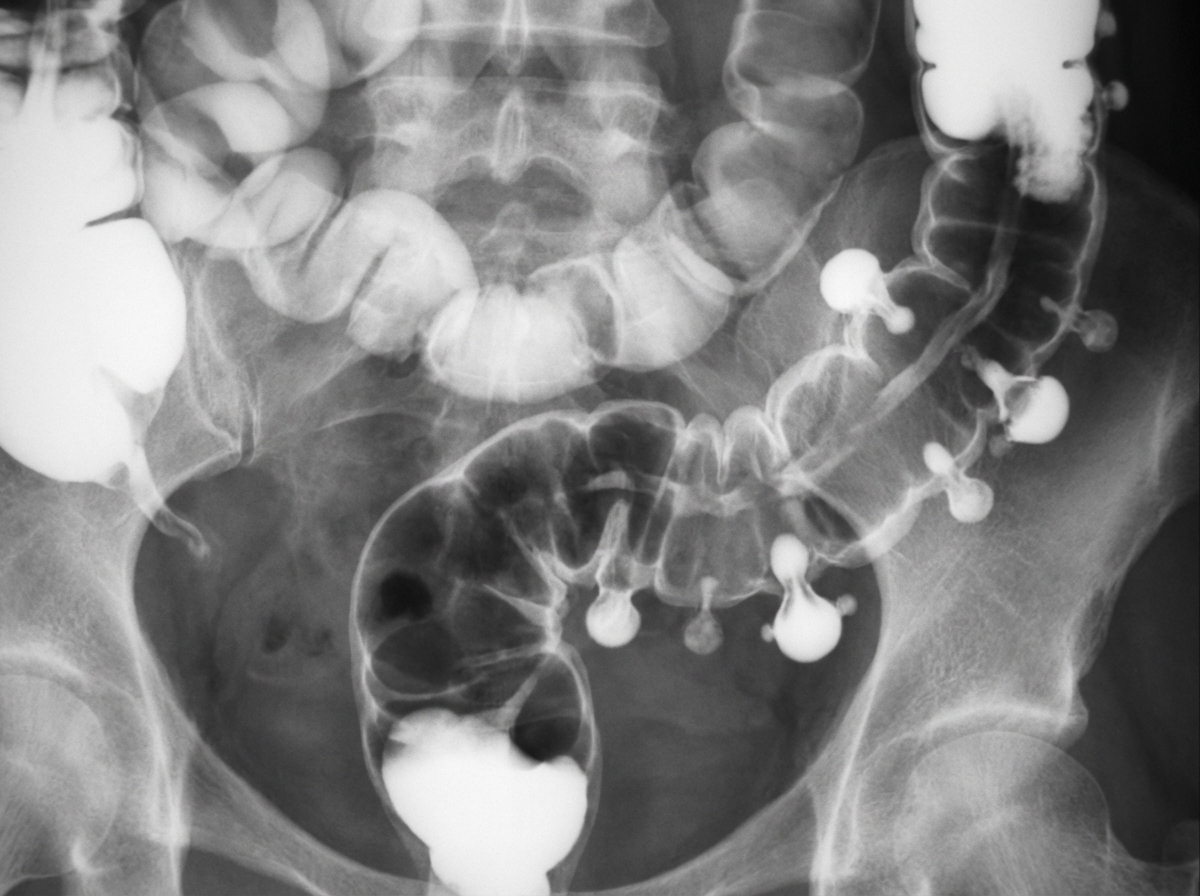

A 38-year-old patient complains of rectal bleeding, tenesmus and mucous discharge. On examination patient is found to have anemia, hypoproteinemia and electrolyte disturbance. On radiological examination this is the presentation of the patient. Which of the following statement is false?

Explanation: ***50 % risk of developing cholangiocarcinoma*** - The risk of **cholangiocarcinoma** in patients with ulcerative colitis and **primary sclerosing cholangitis (PSC)** is significantly increased, but it is not 50%. The lifetime risk of cholangiocarcinoma in PSC patients is approximately **7-10%**. - The image provided depicts a **barium enema** showing signs consistent with **ulcerative colitis**, characterized by diffuse inflammation. The patient's symptoms (rectal bleeding, tenesmus, mucous discharge, anemia) are also classic for **ulcerative colitis**. *Most common site for this condition is rectum* - **Ulcerative colitis** nearly always involves the **rectum** (proctitis) and extends proximally in a continuous fashion. - Rectal involvement is a hallmark of ulcerative colitis, differentiating it from Crohn's disease which can have skip lesions and spare the rectum. *Sacroiliitis and ankylosing spondylitis are associated* - Ulcerative colitis is associated with several **extraintestinal manifestations**, including **arthropathies** like sacroiliitis and ankylosing spondylitis. - These conditions are part of the **spondyloarthropathy** spectrum and frequently occur in patients with inflammatory bowel disease. *Campylobacter infection can mimic early phase of this condition* - **Acute bacterial infections** of the colon, such as those caused by **Campylobacter**, **Shigella**, or **Salmonella**, can cause colonic inflammation, bloody diarrhea, and abdominal pain that may resemble the initial presentation of ulcerative colitis. - Differentiating between infectious colitis and inflammatory bowel disease often requires stool cultures, endoscopy, and biopsy. *Continuous inflammation starting from rectum extending proximally* - This is a **classic and defining feature** of ulcerative colitis - inflammation begins in the rectum and extends proximally in a **continuous, uninterrupted pattern** without skip lesions. - This continuous pattern distinguishes UC from Crohn's disease, which characteristically shows **skip lesions** with areas of normal mucosa between inflamed segments.